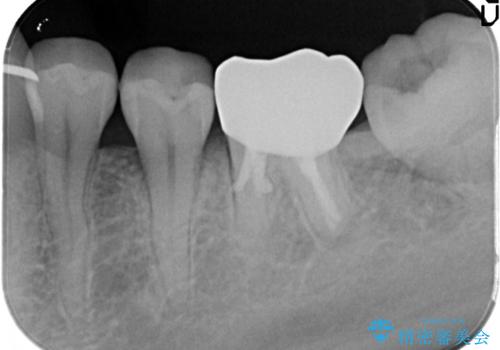

セラミッククラウンにて下顎の左右の歯にセラミッククラウンを装着する計画としました。

目立つところの銀歯がなくなり、審美的な改善ができました。